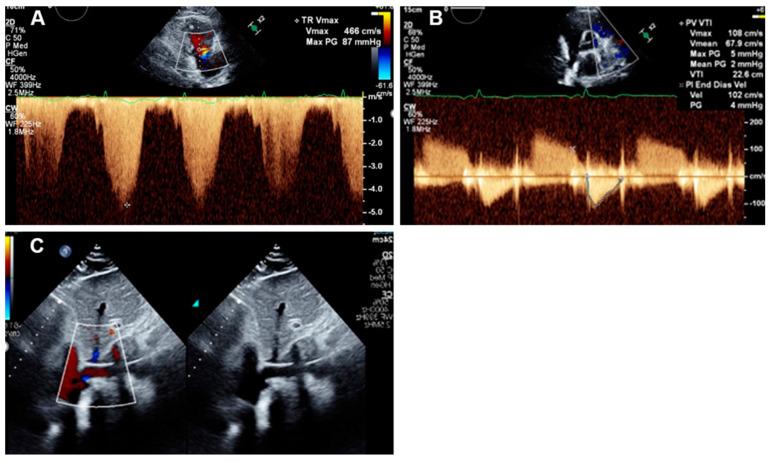

肺动脉搏动指数(PAPI)是一种反映右心室(RV)功能的新型血流动力学参数。PAPI已被证明在预测左心室辅助装置(LVAD)植入、急性右心室梗死以及慢性右心室衰竭患者的预后方面是有用的。估计PAPI的标准方法是在右心导管检查(RHC)期间;然而,基于超声心动图的PAPI也被证明是准确的。在本研究中,我们评估了基于超声心动图的PAPI预测急性肺栓塞(PE)患者预后的能力。

共有177例急性PE患者(平均年龄67±15岁,男性占54.1%)纳入研究。PAPI是根据标准经胸超声心动图测量值计算得出的。

27%的患者需要氧气支持,5.6%的患者接受机械通气,7.3%的患者接受强心支持。整个队列的30天死亡率为8.3%。较低的PAPI测量值与30天死亡率增加(<0.05)、右心室衰竭发生率较高(<0.001)以及需要强心支持(<0.05)相关。PAPI与需要氧气支持(=0.59)、机械通气(0.06)或住院时间(LOS)(=0.414)之间无关联。在预测死亡率和右心室衰竭方面,PAPI优于三尖瓣环平面收缩期位移(TAPSE)。

超声心动图得出的PAPI在预测急性PE患者的右心室衰竭和死亡率方面是可行的,且优于TAPSE。